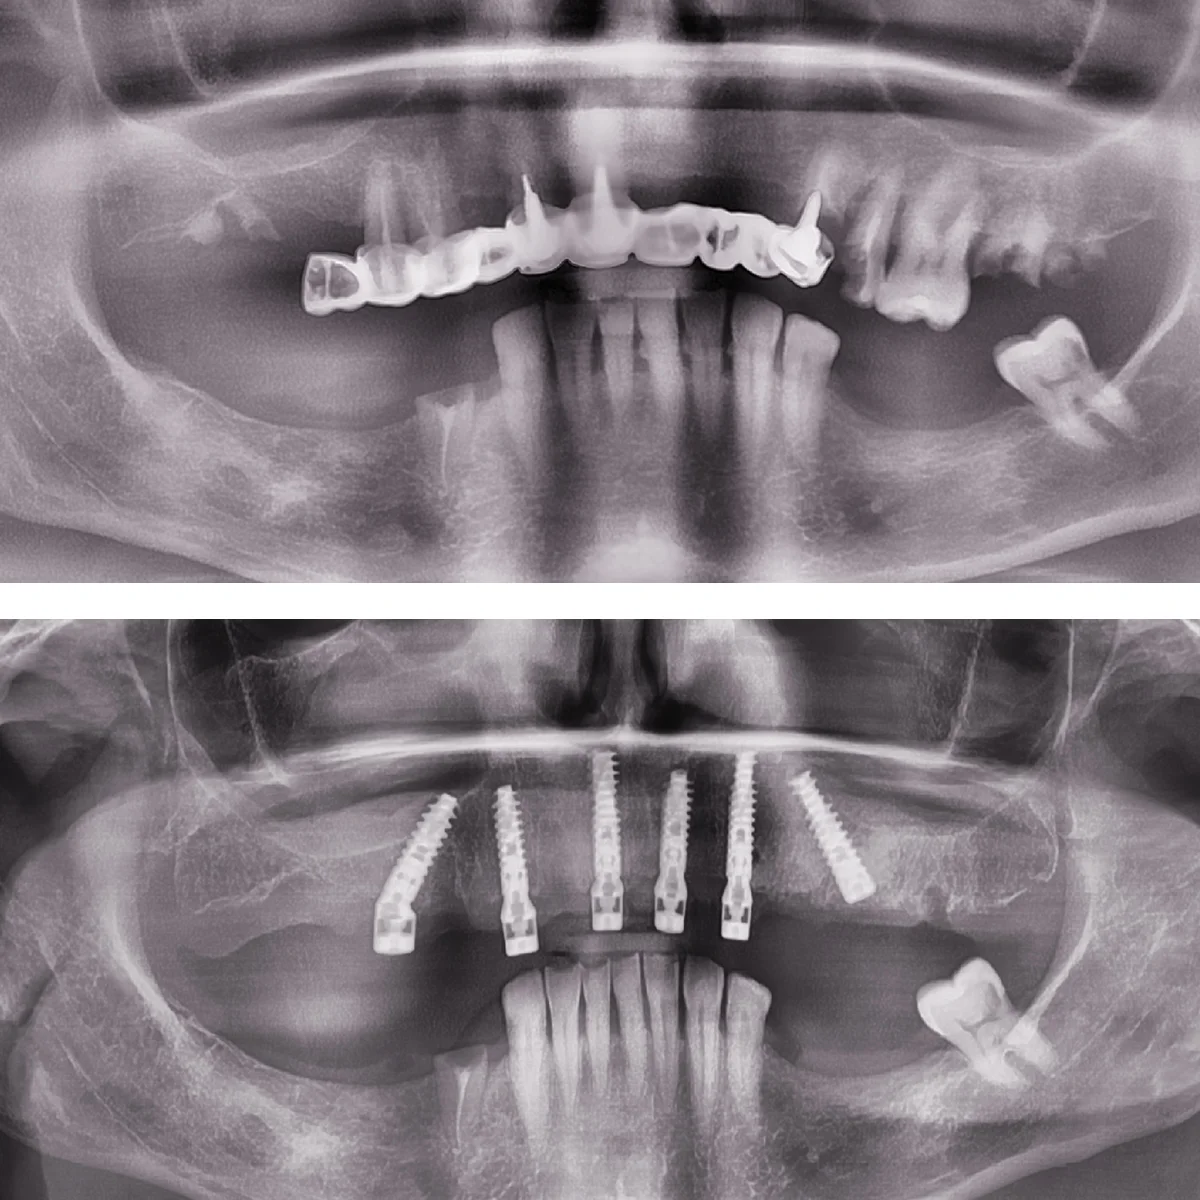

Dinți Ficși în 8-24 de ore pe implanturi dentare cu tehnica All-on-4/All-on-6 este cea mai eficientă și rapidă metodă de restaurare totală a danturii.

Intervenția chirurgicală explicată

Care sunt etapele până la efectuarea intervenției de dinți ficși

- Intervenția chirurgicală

- Aplicare lucrare provizorie pe implanturi